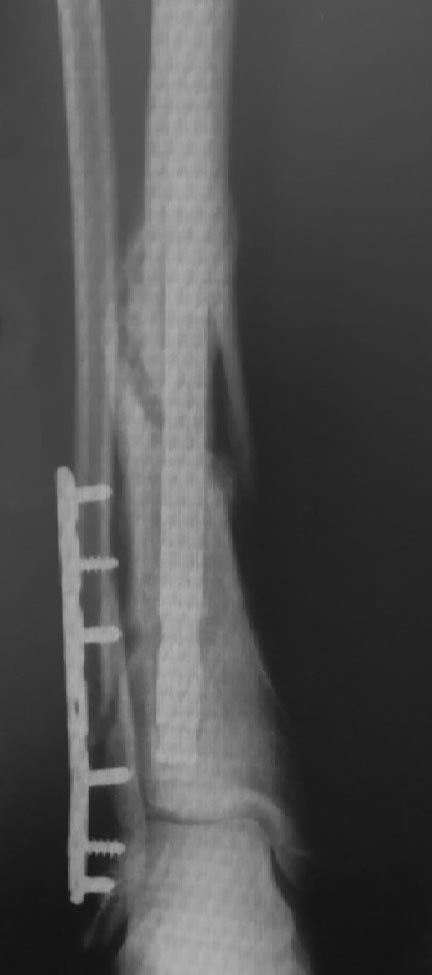

Молодой пациент 30 лет, 5 мес. назад прооперирован по поводу открытого перелома (2 ст) большеберцовой кости (стержень), малоберцовой кости (пластина). В течение указанного времени удален проксимальный статический винт, удален один дистальный винт в виду его миграции. Местные ткани - без проблем.

Нет другой проекции. Добавить винты дистально - не имеет смысла, деротационный момент уже не нужен ввиду наличия мозоли. Более толстый стержень - этот стоит плотно, в проксимальном полностью занимает канал, рассверливание истончит кортикал и нарушит кровообращение в кости. Менять стержень - на сегодняшний день "золотой стандарт" для голени ? На пластину?? По данному снимку идет формирование гипертрофической мозоли, для открытого перелома по срокам консолидация за 5 месяцев даже при БИОСе редко может состояться. Ничего делать не нужно, через 2 - 3 месяца срастется. Даже если мозоль по внутренней поверхности не появится (нежизнеспособный отломок?) - скорее всего проблемы в этом не будет.

На снимке очень хорошая мозоль и сращение идёт полным ходом.

Вы удалили проксимальный статический винт - динамизация по всей видимости. На каких сроках? И может нужно было перерубить малоберцовую выше пластины, для равномерной компрессии?! Она стоит распоркой и могла привести к возникновению, имеющейся сейчас, антекурвации. А может она была изначально. Варус меня беспокоит меньше.

Проблема не определена! При открытых оскольчатых переломах более 1 ст.в н/3 голени сроки сращения как минимум в 1.5-2 раза длиннее даже при ограниченной инвазивности с применением аппаратов внешней фиксации. Межотломковый регенерат - отчётливо виден. Стабильность стержня - наверно достаточная. Скорее избавится от конструкций? Целесообразность?